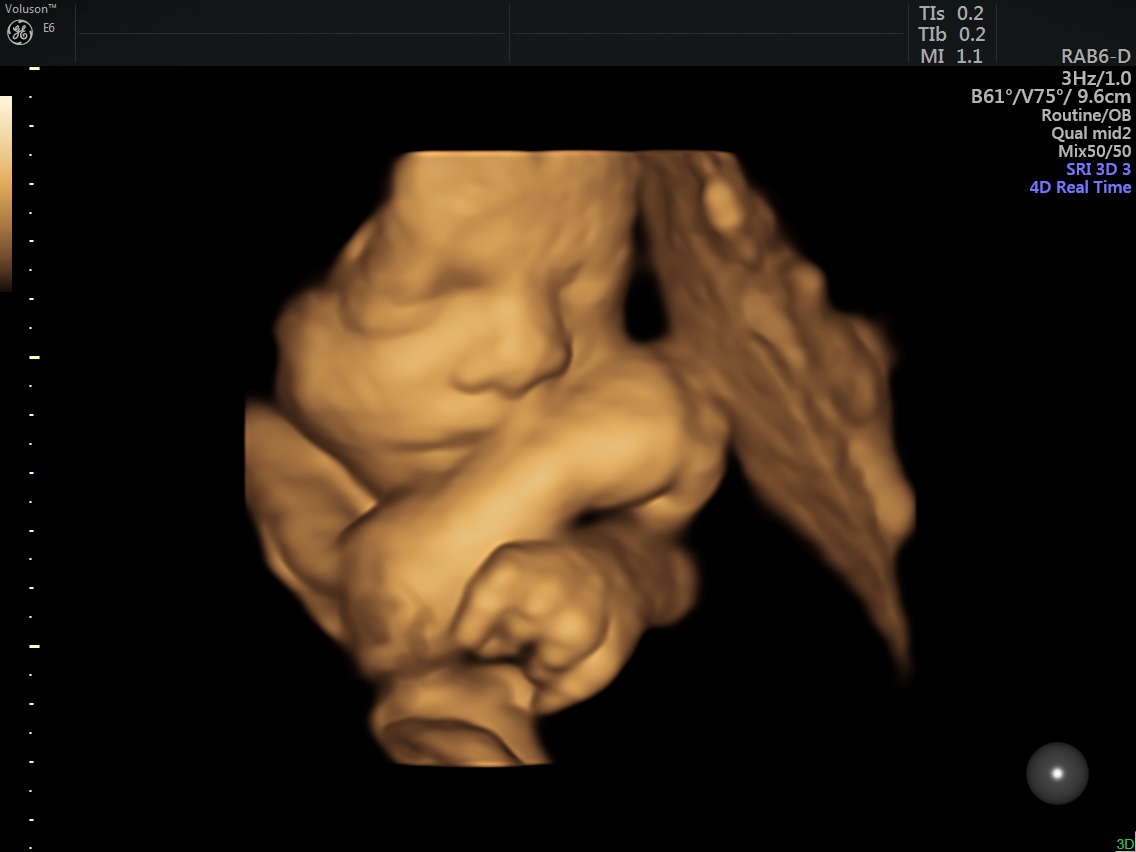

I’ve been sick off and on through this pregnancy but no complaints, just little uncomfortable here and there and little sleep, but I know the gift is so worth it. Little miss (name still being decided on by Ryken) is growing well, heart rate was 135-140 this week, and we got to see her beautiful face last week. Chubby cheeks and lots of sass already, and she looks a little like Ryken (no surprise there, she is technically her fraternal twin) – crazy to think right? Welcome to IVF and the incredible ability to freeze embryos. Little Miss has been growing well, despite the 2-vessel vs 3-vessel umbilical cord. My Dr says generally, they may slow down growth after 30ish weeks, so we will be doing a growth ultrasound in 2 weeks and monitoring her closely til she arrives!